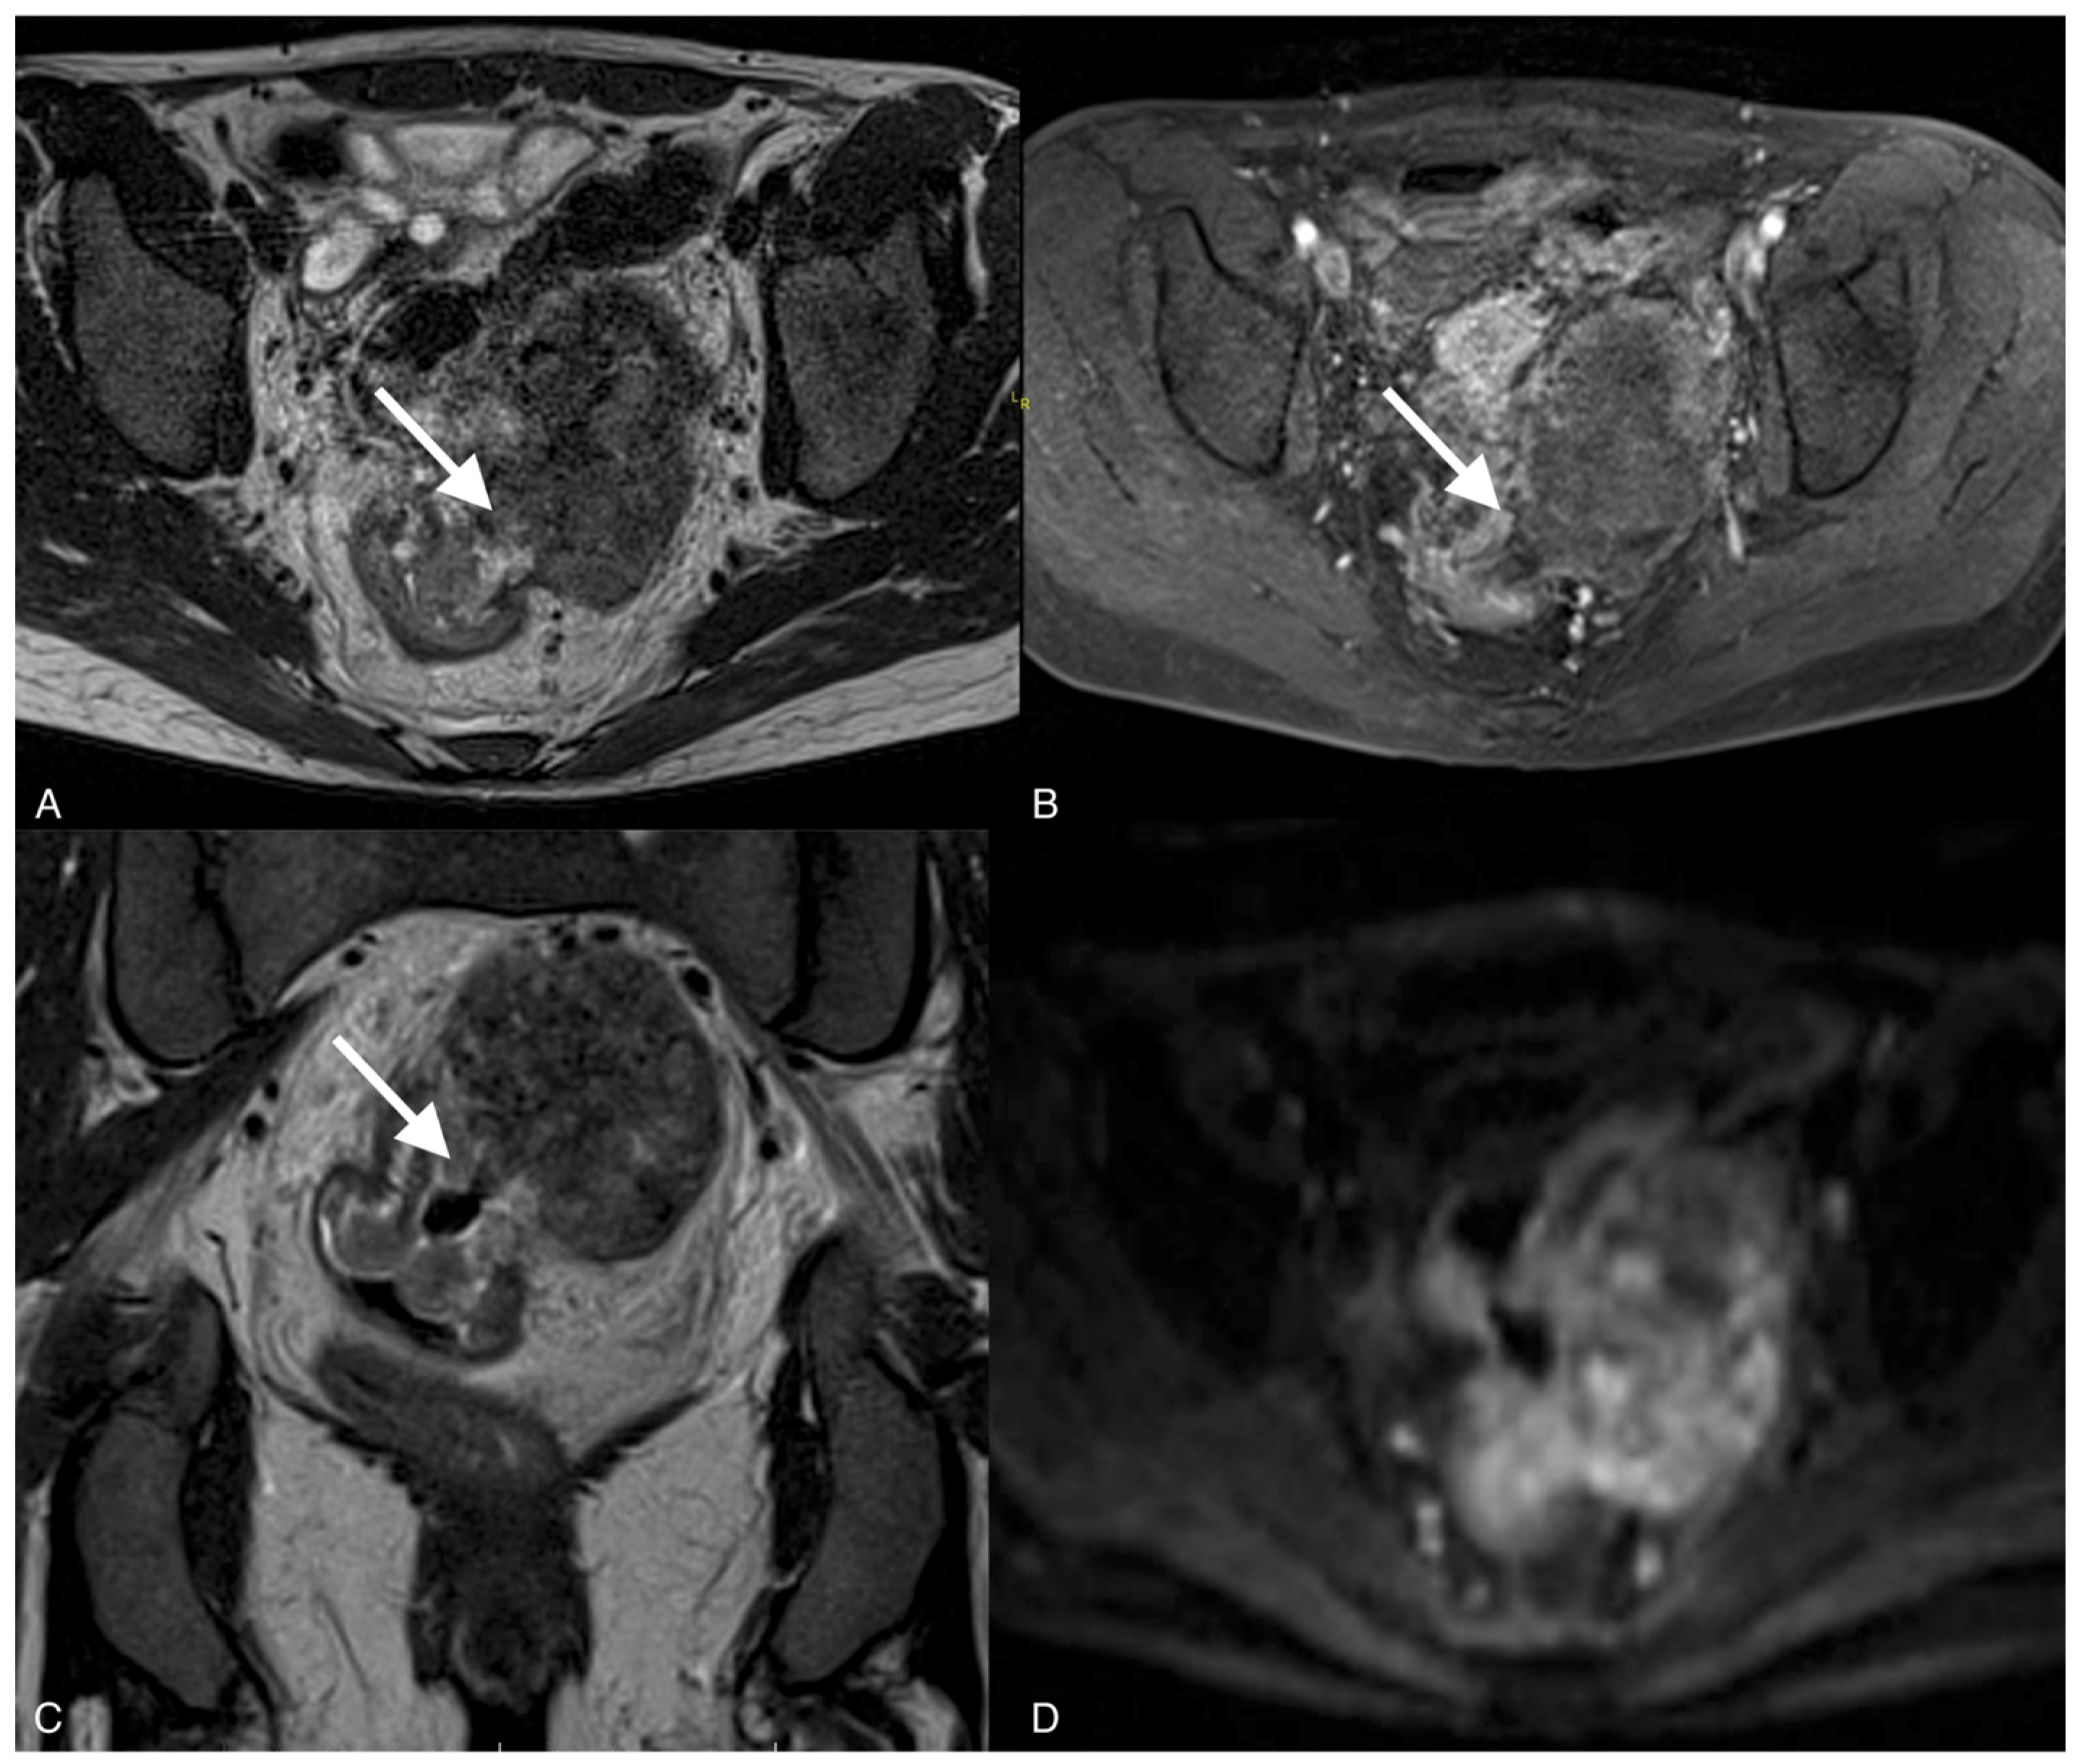

Figure 4.

Images of a 37-year-old woman with a recurrent tumor of high-grade serous ovarian cancer with fistula between tumor and sigmoid colon. MRI T2-weighted images obtained in axial plane (A), coronal plane (B), and T1 post-contrast (C) show a large solid/cystic tumor and the fistula (arrows) between tumor and sigmoid colon. DWI (b1200) shows restricted diffusion in the tumor but not in the fistula (D).

To confirm the suspected fistula, the patients were referred for MRI. In all cases, the fistula was visible on the MR images, showing hypointensity on the T2 and T1 post-contrast sequences but no restricted diffusion on the DWI sequence. The fistula in one of the patients was hyperintense on T2 images and hypointense on T1-weighted images and showed restricted diffusion on DWI.

Fluid-containing fistulas appear as a high signal on T2-weighted images and STIR, while gas-containing fistulas have a low signal in all sequences and demonstrate contrast enhancement. Old, healed fistulas typically demonstrate low T1 and T2 signals without contrast enhancement, reflecting fibrosis [19]. Our study showed that fistulas were hypointense on T2 sequences and hypointense on T1 sequences, and the best sequences to diagnose fistulas on MRI were T2 sequences and late arterial phase post-contrast T1 sequences, which suggest no active inflammatory processes or necrosis.

The study showed that the DWI sequence was not superior to the other sequences in diagnosing fistulas on MRI, except for one of the patients in whom an acute inflammatory process was involved. Recent studies have shown that diffusion-weighted images are useful for diagnosing fistulas in the pelvis and determining whether they involve acute inflammation. However, DWI alone was not superior to T2 and T1 sequences with contrast [20]. DWI can show restricted diffusion in the tumor, which has an important role in the detection, characterization, and definition of local tumor spread [17].